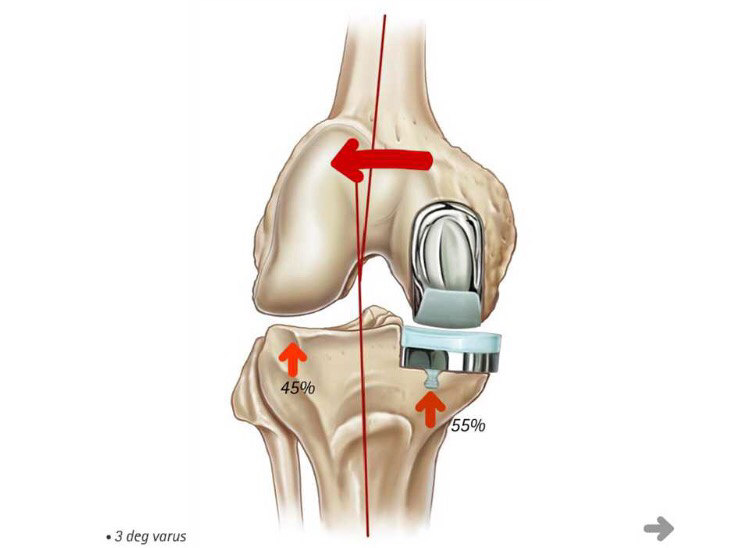

膝关节单髁置换术

膝关节单髁置换术可用于治疗膝关节单间室骨关节炎患者,可以说这是一